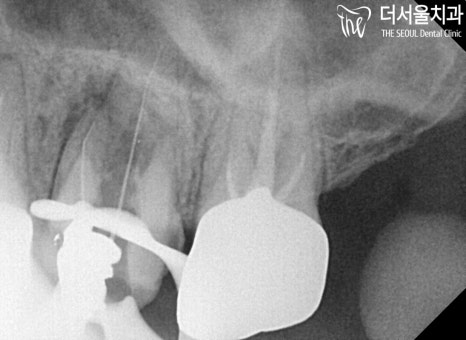

좀 더 정확한 진단을 내릴 수 있도록

X-Ray 촬영을 통하여

이미 잇몸 속은 시커멓게

변해있는 것을 볼 수 있는데요.

어쩔 수 없이 치아 재신경치료를

받으셔야 되는 상황이었습니다.